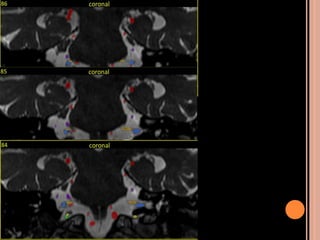

 Schwannomas vestibulares:

Originam-se no conduto auditivo interno; pode se

estender para a cisterna pontocerebelar;

o 5° par (trigêmio): 2° sítio mais acometido;

Achados de imagem NF2

 Schwannomas vestibulares (realce homogêneo

pelo contraste, seria hipo em T1)

 Meningeomas (realce intenso pelo contraste)

 Calcificação assimétrica de plexo corióide

 Schwannomas volumosos se estendendo para a

cisterna pontocerebelar com intensa impregnação

pelo Gd; na sequência em T2 tem hipersinal

heterogêneo;

 Múltiplos nódulos, em T1 pós contraste importante

realce compatíveis com schwannomas;

SCWHANNOMAS

Pequenas lesões no CAI, bem mais caracterizada

nas aquisições volumétricas(3D CISS);

Aspecto de “sorvete de casquinha” quando lesões

maiores com extensão pontocerebelar;

Hipo em T1 e hiper heterogêneo em T2;

Impregnação pelo Gd homogênea se pequenos e

heterogênea se grandes;

 Iso ou hipoatenuante em relação ao parênquima e realce pelo meio

de contraste, no ângulo pontocerebelar;

 Schwannomas vestibulares

 Schwannoma de nervo trigêmio